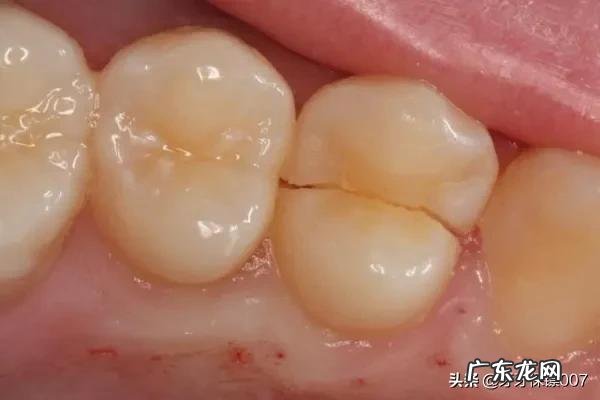

牙齿为什么需要拔除了?牙齿,在医生的眼中是极其重要的,但是当感染不易控制及剩余的牙体组织过少不易修复时,就只有采取拔牙的操作了 。

如牙齿折裂,其裂纹可以深达根尖,口腔zhi疗不能够很好的封闭,因此需要及时拔牙;牙齿形成短短的残根,甚至缺损至牙龈下面,根管zhi疗后没有足够的长度进行恢复,也需要拔牙;当牙齿周围组织感染较重,经常牙龈红肿、流脓,且松动非常明显,一般也需要拔牙 。